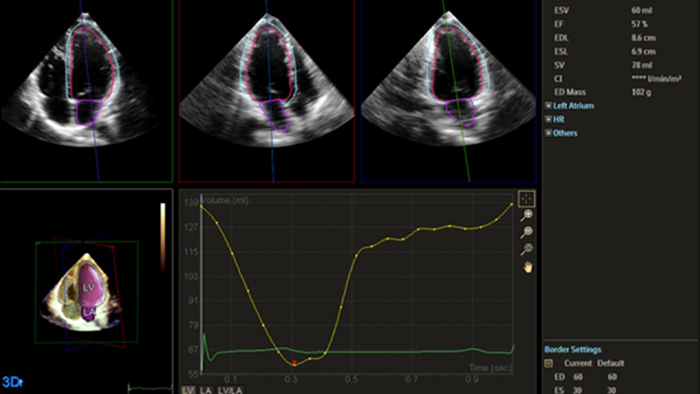

Echo is often the first cardiac imaging test that’s performed for patients with suspected heart failure. An echocardiogram gives us a wealth of information on cardiac structure and function using both 2D and 3D tools. Echocardiography can help us understand the etiology of heart failure in many situations. I routinely use information derived from both 2D and 3D analysis and strain to better understand my patients. AutoStrain, Dynamic HeartModel and Auto RV are invaluable tools that are used both in the diagnosis and surveillance of patients with heart failure.”

Fast and reproducible tools with integrated workflows

Robust and reproducible imaging tools are important to diagnose and monitor disease progression in heart failure. Current guidelines support the use of advanced echocardiography tools such as longitudinal strain and 3D assessment of LV and RV volumes and function.

Quantification through Dynamic HeartModel.